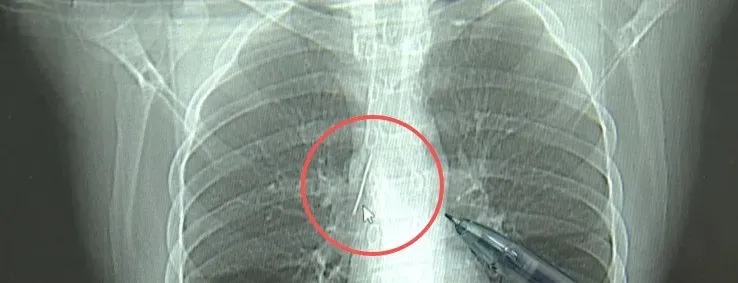

近日,安徽17岁小伙小陆参加征兵体检,胸片后果显示:胸腔内有一处金属高密度影,形态细长,像一根针。

进一步的CT检查确认,异物是一枚金属针,斜插在肺组织内,位置十分凶险。

杭州市第一人民医院心胸外科副主任冯兴说:“我们看到这个针的尖锐部,正好指向他体内的一个大血管,边上是上腔静脉和胸主动脉,因此这个针稍有不慎,就有或许造成周边血管的损伤,甚至危及生命。”

医生推测,那枚针很或许就是在那时候扎入体内的。针在小陆体内滞留了十几年,既没有引发感染,也没有造成气胸,堪称医学奇迹。上周四,医院为小陆实施了mini单孔胸腔镜微创手术,切口仅两厘米左右,胜利将针完整取出。